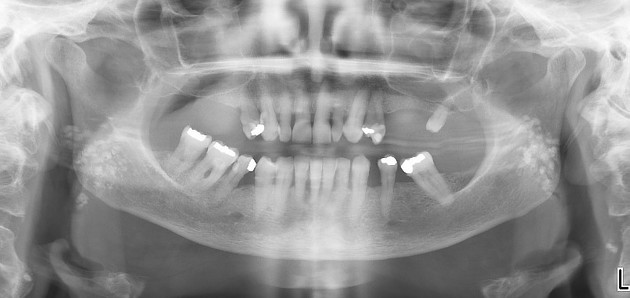

1. What condition can be seen in the following X ray? ( solid arrow)

the calcification within Stensen's duct of parotid